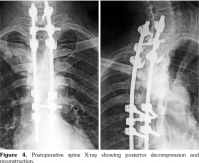

Laboratory examination revealed a slightly elevated C-reactive protein level (16 mg/L) and erythrocyte sedimentation rate (40 mm). Serum levels of calcium, albumin and phosphorus were within the normal range. Blood cell counts, liver tests, and renal function were unremarkable. Blood cultures, urinanalysis, tumor markers, and serodiagnosis for brucella were negative. Tuberculosis skin test was negative. Spine magnetic resonance imaging showed low T1, high T2 signal and contrast enhancement in the T4/T5 and L3 vertebral body and in the T4/T5 disk (Figure 1). Sacroiliac joints were normal. Computed tomography-guided biopsy of the T4/T5 disc demonstrated nonspecific inflammation and culture of this specimen was negative. Computed tomography scan of the sternoclavicular joints revealed hyperostosis and erosions involving the sternum as well as medial end of clavicle (Figure 2). Clavicular biopsy showed irregular sclerotic trabeculae. Human leukocyte antigen B27 typing was positive.

Radiological signs of SAPHO may sometimes be difficult to differentiate from infectious spondylodiscitis and even tumors, leading to a diagnostic delay. Indeed, the intervertebral disc may be narrowed, and, in 10% of cases, magnetic resonance imaging shows high signal intensity on T2-weighted images and gadolinium enhancement, simulating infectious spondylodiscitis.(3-7)